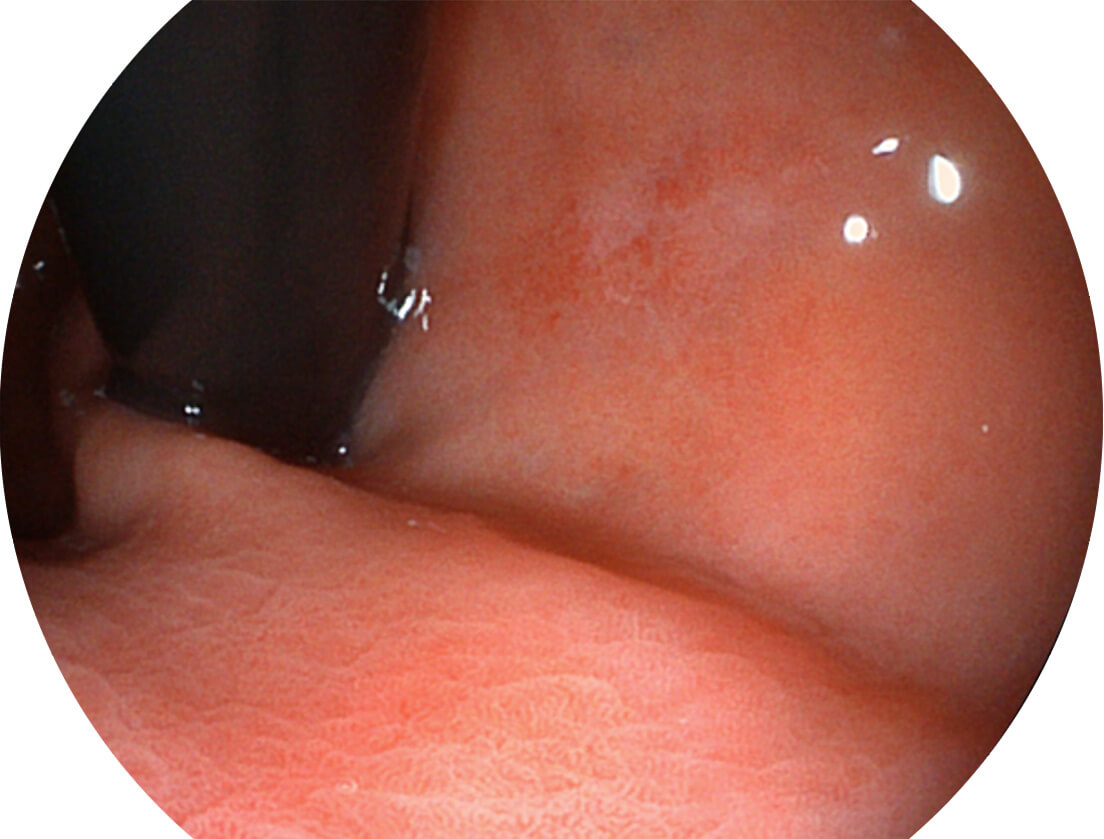

• 白光圖像 SFI圖像

• 白光圖像 VIST圖像